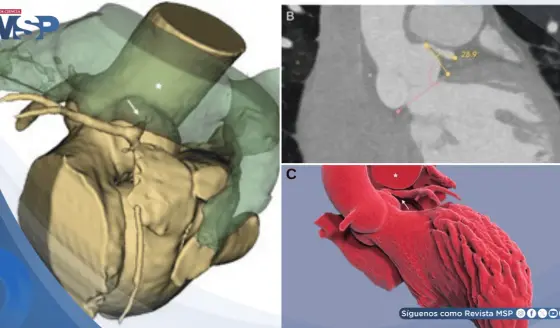

El Bayamón Heart & Lung Institute transmite casos en vivo a CTO Plus 2026

Regurgitación Mitral Degenerativa